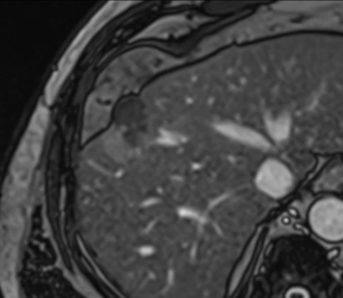

A small hepatocellular carcinoma is shown on MRI. It demonstrates arterial enhancement after gadolinium injection.

The same lesion is visible on non-contrast MRI (Trufi), ensuring easy targeting with MRI guidance.

Real-time MRI guidance is used to place the first cryoprobe into the lesion.

The ice ball is well visualised on all MRI sequences, ensuring complete coverage of the tumour with margins to spare.